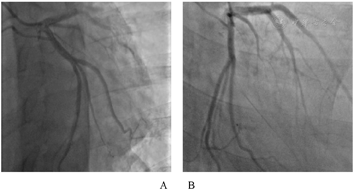

在征求患方同意、拟完善冠状动脉造影检查。2014年1月15日局麻下行冠脉造影术,术中见左冠状动脉走行自然,比光滑,未见明显狭窄;但右冠状动脉显影见近端以远闭塞,近段至中段桥侧支形成。综合患者病史特点、体征、检查检验及冠脉造影等,最后诊断:冠状动脉粥样硬化性心脏病:缺血性心肌病,右房、右室增大,三尖瓣重度关闭不全,心房颤动,心功能II级。